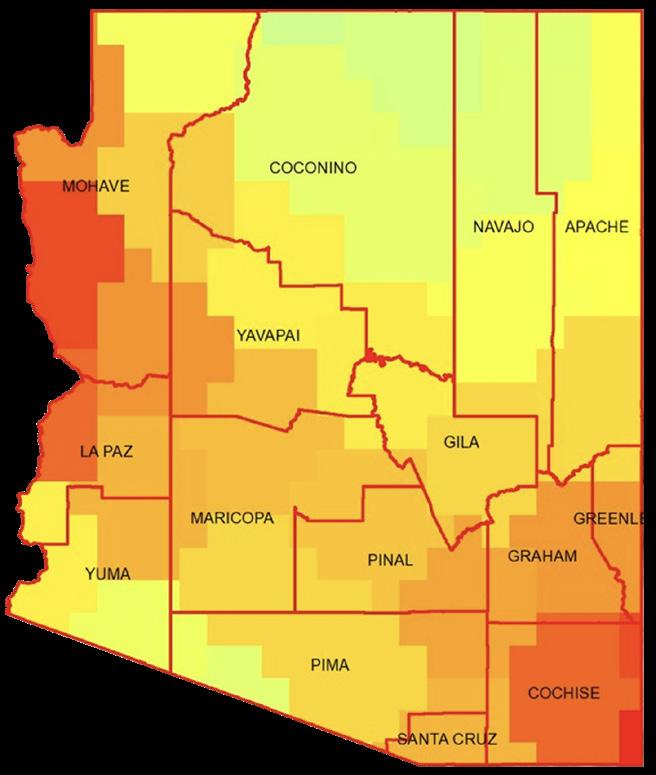

If a disaster struck Arizona, vulnerable communities would be hardest hit, based on many factors such as socioeconomic status, racial and ethnic backgrounds, household characteristics, and housing type. For the first time, the state now can take factors specific to Arizona, such as access to care, heat resilience, rent and utility burden, and food insecurity, into account when managing health and safety hazards.

In collaboration with the Arizona Department of Health Services, the Health Observatory at ASU led an initiative to develop an advanced, Arizona-specific social vulnerability index that objectively ranks communities that would be disproportionately affected by health hazards.

Using these new metrics, the Health Observatory at ASU discovered that many locations were more vulnerable to disaster events than initial projections from the Centers for Disease Control and Prevention indicated. The new knowledge can protect the state’s most vulnerable residents by proactively supplying these areas with additional resources ahead of disasters and other health and safety hazards.

Each year more than 10,000 Arizonans are diagnosed with Valley fever, an infection caused by breathing in spores of the fungus Coccidioides. When soil that contains the spores is disturbed — through construction, wind or even walking — the spores can be lofted into the air and potentially inhaled. While most people who get Valley Fever recover from the illness, the infection sometimes leads to severe complications or even death.

The Health Observatory at ASU is helping public health and health care leaders to better target their efforts to reduce the impact of the disease.

The Health Observatory is building upon the prior work of TGen, a nonprofit medical research institute based in Arizona, which analyzed thousands of air filters around the Phoenix metropolitan area for the presence of Coccidioides. Previously identified factors such as increased temperatures, higher winds and decreased soil moisture increased the likelihood of Coccidioides

being detected in the air. These factors, however, do not fully explain all the observed variation in the fungus’ presence in the air filters.

Working with leading researchers in the field, the Health Observatory is now investigating additional factors — integrating weather, land cover disturbance and other environmental datasets with the Coccidioides air filter data to further understand drivers of aerosolization through statistical models.

Increased understanding of what drives Coccidioides up into the air we breathe may help lessen exposure to the fungus and protect the health of thousands of Arizonans for years to come.